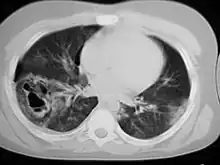

Computed tomography

Computed tomography (CT scanning) is a more sensitive test for pulmonary contusion,[6][33] and it can identify abdominal, chest, or other injuries that accompany the contusion.[38] In one study, chest X-ray detected pulmonary contusions in 16.3% of people with serious blunt trauma, while CT detected them in 31.2% of the same people.[45] Unlike X-ray, CT scanning can detect the contusion almost immediately after the injury.[43] However, in both X-ray and CT a contusion may become more visible over the first 24–48 hours after trauma as bleeding and edema into lung tissues progress.[46] CT scanning also helps determine the size of a contusion, which is useful in determining whether a patient needs mechanical ventilation; a larger volume of contused lung on CT scan is associated with an increased likelihood that ventilation will be needed.[43] CT scans also help differentiate between contusion and pulmonary hematoma, which may be difficult to tell apart otherwise.[47] However, pulmonary contusions that are visible on CT but not chest X-ray are usually not severe enough to affect outcome or treatment.[37]